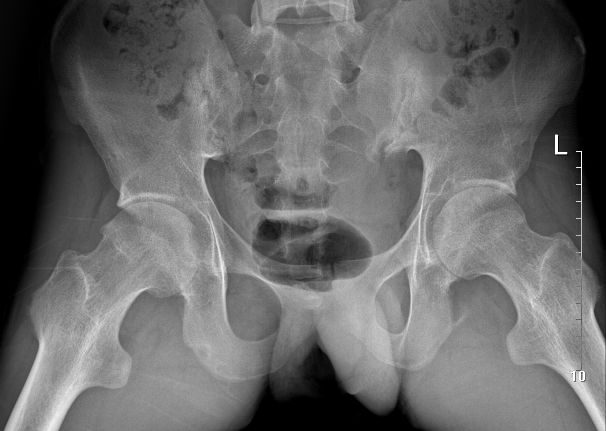

图:强直性脊柱炎伴轻度髋关节结构破坏改变

例1:21岁男性,AS患者,双髋关节疼痛伴活动受限4年